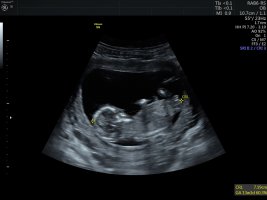

• E1805736-55BC-4605-9939-39F2CC362BF1.jpeg

E1805736-55BC-4605-9939-39F2CC362BF1.jpeg

160,7 KB · Görüntüleme: 390